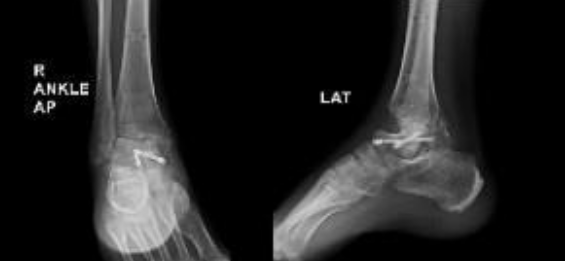

We present the case of a 37-year-old male who sustained a right ankle injury following a road traffic accident. Initial imaging revealed fractures of the talus, medial malleolus, and lateral malleolus, along with a talonavicular joint dislocation. The patient underwent open reduction and internal fixation of the talus using two cannulated screws, along with application of an ankle-spanning external fixator. The external fixator was retained for 2 months during which the patient was kept non-weight bearing, following which the external fixator was removed, and weight-bearing was initiated. Over the subsequent months, the patient developed persistent ankle pain, difficulty with weight-bearing, and significant functional limitation (Fig. 1).

Figure 1: Pre-revision radiographs obtained 2 months after initial open reduction and fixation, demonstrating collapse of the talar body with screws in situ, along with loss of ankle congruency.

Physical examination revealed visible deformity of the ankle, including hindfoot varus and cavus with severely limited ankle joint range of motion and minimal subtalar joint motion compared to the contralateral limb. Pain and functional status were assessed using the Visual Analog Scale (VAS) and American Orthopaedic Foot and Ankle Society (AOFAS) scores pre and postoperatively. Radiographs obtained during follow-up showed collapse of the talus. A computed tomography scan performed subsequently demonstrated union of the medial and lateral malleoli, with non-union of the talus and sclerosis of the talar dome consistent with AVN (Fig. 2).